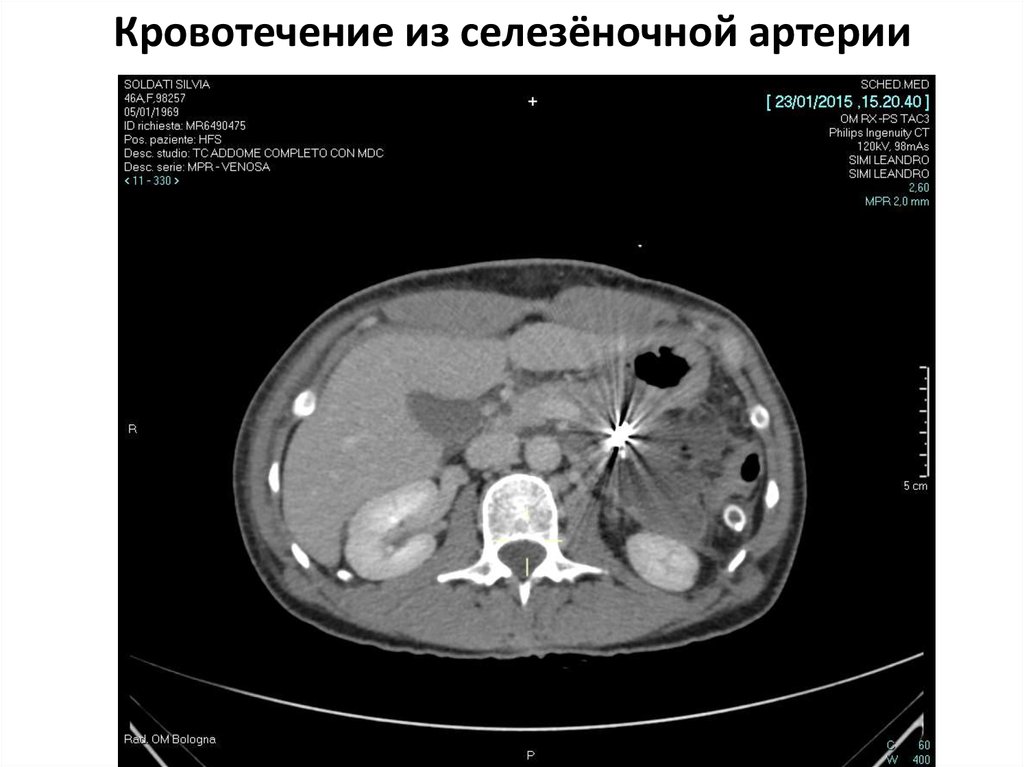

Кровотечение из селезёночной артерии

В сосудистой программе

при компьютерной томографии выявлена псевдоаневризма селезеночной

артерии (1,0 х1,5 см), прилежащая к псевдокисте